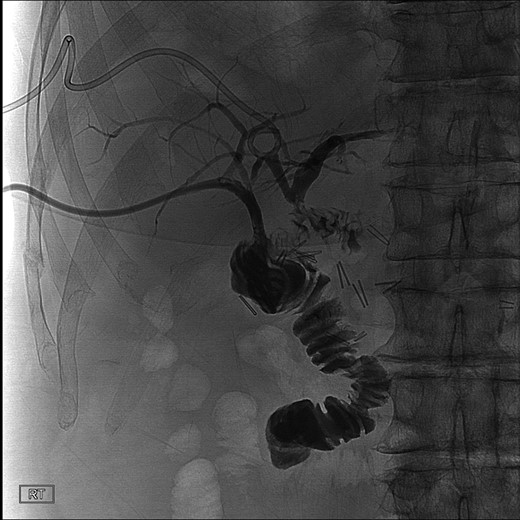

During this operation, the porta was dissected and the common and proper hepatic arteries were identified and preserved. We were unable to palpate the previously placed percutaneous biliary catheters due to the high placement above the hilum at the level of multiple clips. We transected the CBD distally and removed numerous clips, finally noting bile drainage, but were unable to identify a cholangiogram catheter. We then identified a second tubular structure more lateral to the duct. We elected to transect this tissue, identifying a second extrahepatic bile duct. The anterior percutaneous catheter was identified proximally within the duct. An on-table cholangiogram with fluoroscopy was performed noting two separate extrahepatic biliary systems, draining the right and left lobes of the liver, respectively (Figs 3 and 4). Both distal ducts were ligated to definitively close the orifice to the duodenum and prevent spillage. A Roux limb of jejunum was created and anastomosed in a retrocolic fashion to the two separate hepatic ducts at the level of the hilum. A drain was placed, and there was no evidence of bile leakage.

Intraoperative cholangiogram of the left ductal system through the extrahepatic left CBD.